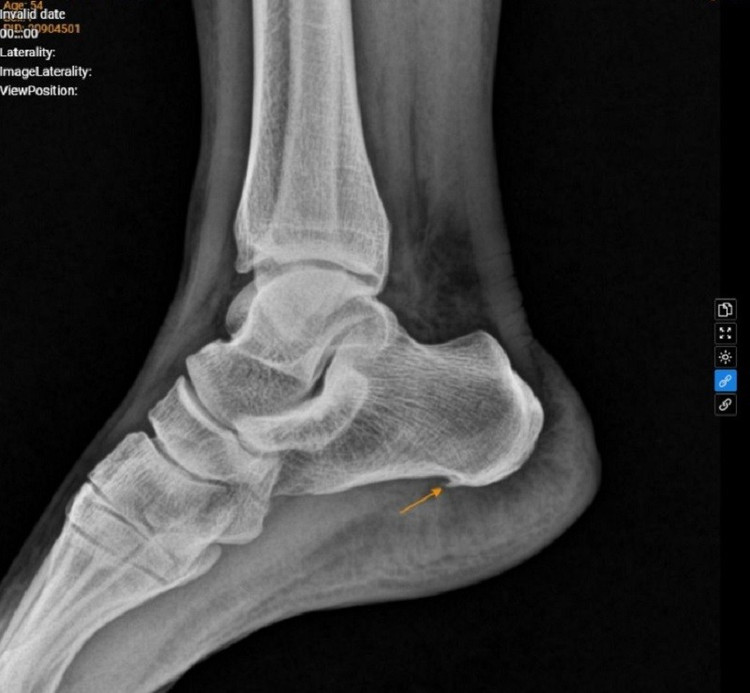

Đối với triệu chứng đau âm ỉ quanh vùng gót chân trái, kết quả chụp Xquang cho thấy, hình ảnh gai xương gót chân trái - nghi ngờ viêm cân gan chân mạn tính.

Xquang thấy hình ảnh gai xương gót bàn chân trái/Ảnh BV medlatec